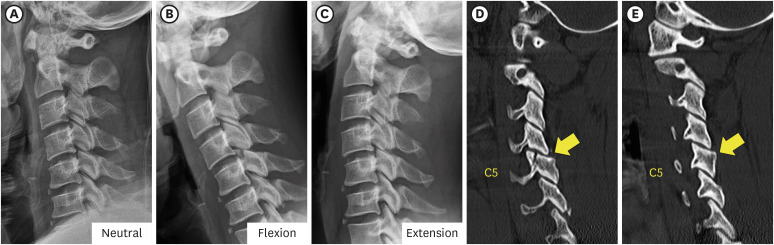

一名 42 岁男子从树上摔下后出现颈部疼痛。脊柱计算机断层扫描(CT)显示右侧 C5 上关节突骨折,无移位。磁共振成像(MRI)证实了骨折和后韧带复合体损伤。起初,由于没有不稳定或椎体错位的迹象,他接受了颈部支撑的保守治疗。然而,出院三天后,右肩无力和右上臂麻木的症状开始突出。X光片和CT显示,C4椎体前滑,C4/5椎面锁定,C5上关节突骨折骨片被锁定的C4下关节突推向前方,侵入神经孔。采用同种异体移植和钢板/螺钉固定,进行了颈椎前路椎间盘切除和融合术(ACDF)。虽然最初的影像学检查未显示有脱位迹象,但外科医生应注意隐匿性不稳定性以及与单侧颈椎面骨折相关的延迟脱位的可能性。

A 42-year-old man presented with neck pain after a fall from a tree. Spine computed tomography (CT) illustrated the right C5 superior articular process fracture without displacement. Magnetic resonance imaging (MRI) confirmed the fracture and injury of the posterior ligament complex. Initially he was managed conservatively with a neck brace as there were no signs of instability or vertebral body misalignment. However, three days after discharge, right shoulder weakness and numbness of the right upper arm became prominent. X-rays and CT showed anterior slippage of the C4 vertebral body and locked C4/5 facet ??a fractured bony fragment of the C5 superior articular process was pushed forward by the locked inferior articular process of C4 and invaded the neural foramen. Anterior cervical discectomy and fusion (ACDF) was performed using allograft and plate/screws fixation. Although initial imaging showed no evidence of subluxation, surgeons should be aware of occult instability and the possibility of delayed dislocation associated with the unilateral cervical facet fracture.